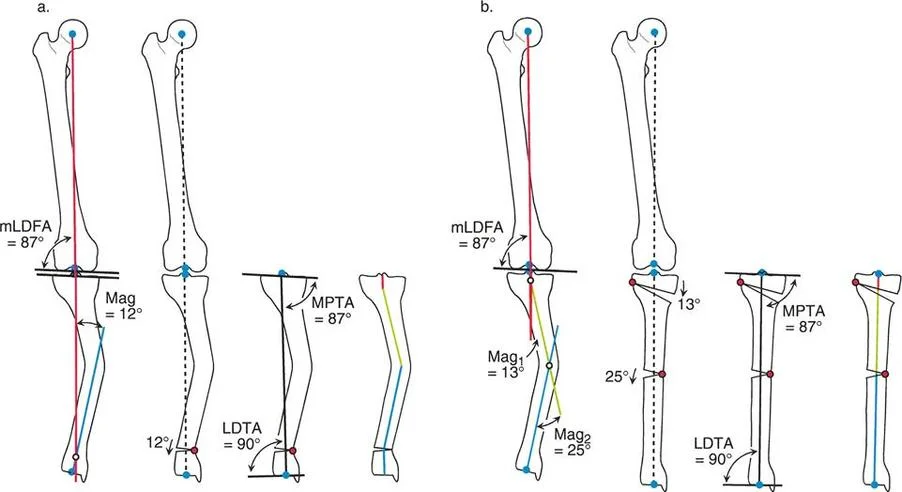

مركز دوران الانحراف (CORA)

يعتبر CORA خاصية أساسية للتشوه في العظم. يُعرّف بأنه نقطة تقاطع خط المحور الميكانيكي (أو التشريحي) القريب وخط المحور الميكانيكي (أو التشريحي) البعيد.

* CORA الحقيقي: هو القمة التشريحية الفعلية للتشوه.

* CORA الحل (Resolution CORA): نقطة نظرية تُستخدم في التشوهات متعددة المستويات حيث تتقاطع المحاور القريبة والبعيدة النهائية، وقد لا تقع هذه النقطة داخل العظم نفسه.

محور تصحيح الزاوية (ACA)

بينما يعتبر CORA حقيقة تشريحية ثابتة، فإن ACA يقع جزئيًا تحت سيطرة الجراح. يمثل ACA النقطة المحورية التي يدور حولها الجزء البعيد من العظم لتحقيق التصحيح.

* الموضع الأمثل: يجب أن يكون ACA موجهًا بشكل عمودي على مستوى التشوه ويمر مباشرة عبر CORA.

مستوى قطع العظم (Osteotomy Level)

مستوى قطع العظم (الشق الجراحي) يقع بالكامل تحت سيطرة الجراح. تحدد العلاقة الهندسية بين مستوى قطع العظم، وACA، وCORA النوع الدقيق للتصحيح الناتج، وتحدد ما إذا كان سيحدث تشوه ثانوي غير مقصود (مثل الانزياح غير المرغوب فيه).

إن فهم العلاقة المكانية بين القطع، والمفصلة، وقمة التشوه هو سر التصحيح الخالي من العيوب. تحدد قواعد بالي لقطع العظم النتائج الميكانيكية لخطتك الجراحية:

القاعدة الذهبية الأولى: القطع والمفصلة عند مركز الانحراف

عندما يمر كل من قطع العظم وACA مباشرة عبر CORA، يتم تصحيح التشوه الزاوي بشكل مثالي. يتم استعادة المحور الميكانيكي، ولا يوجد انحراف في المحور الميكانيكي (MAD)، وتبقى أجزاء العظم القريبة والبعيدة متوازية تمامًا. هذا هو السيناريو المثالي، والذي غالبًا ما يتحقق بقطع عظم وتدي بسيط (فتح أو إغلاق) عند قمة التشوه.

القاعدة الذهبية الثانية: المفصلة عند مركز الانحراف والقطع بمستوى مختلف

في بعض الأحيان، قد يكون قطع العظم مباشرة عند CORA غير ممكن سريريًا بسبب سوء حالة الجلد، أو وجود أدوات جراحية سابقة، أو مشاكل في جودة العظم في منطقة الكردوس/الجذع. إذا بقي ACA عند CORA، ولكن تم إجراء قطع العظم عند مستوى مختلف (أقرب أو أبعد عن CORA)، فسيتم تصحيح التشوه الزاوي بالكامل. ومع ذلك، ستنزاح نهايات العظم عند موقع قطع العظم بالنسبة لبعضها البعض.

* النتيجة السريرية: يؤدي هذا إلى "نتوء" أو تعرج في المحور التشريحي، لكن المحور الميكانيكي العام وتوجيه المفصل يظلان متوائمين تمامًا.